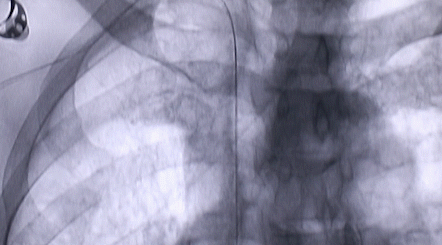

按照術(shù)前制定的方案,郭穎強(qiáng)主任和楊金保博士首先嘗試開通閉塞的右腎動脈,但由于血栓機(jī)化、鈣化嚴(yán)重,右腎動脈難以開通。遂謹(jǐn)慎擴(kuò)張狹窄的左腎動脈,并成功植入一枚支架。之后經(jīng)過反復(fù)旋磨、抽吸,順利開通髂動脈,但腹主動脈閉塞段仍難以擴(kuò)通。此時,患者居高不下的血壓很快恢復(fù)到正常水平。